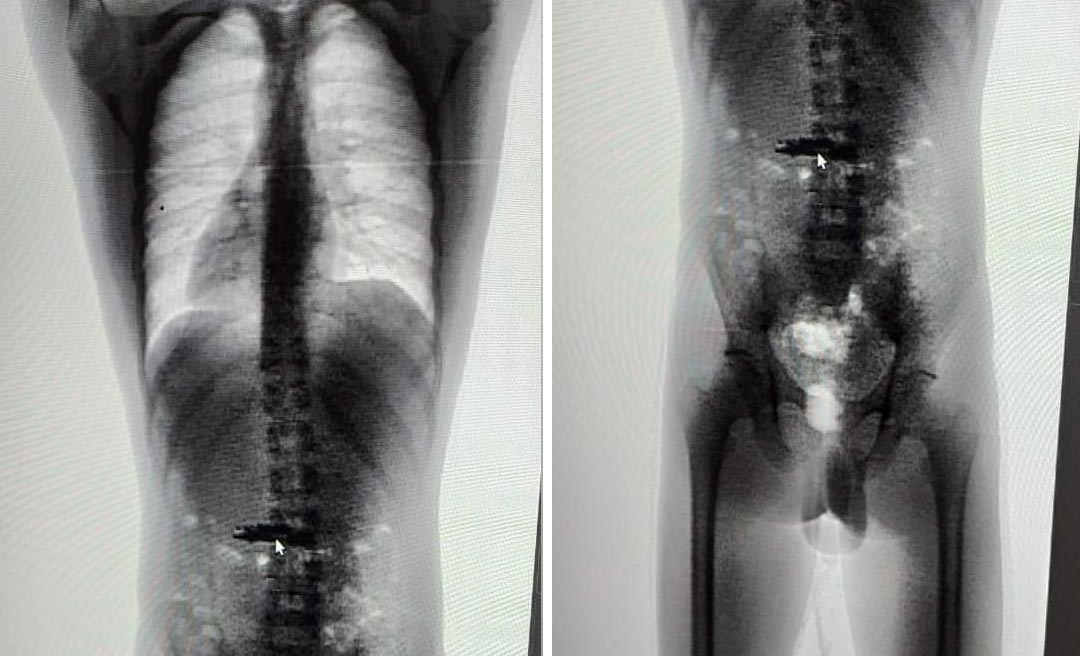

Os suspeitos foram encaminhados até o aparelho de scanner corporal, onde foi identificado a presença de dois celulares na região do estômago. Um dos reeducandos conseguiu expelir o eletrônico por meio de vômito.